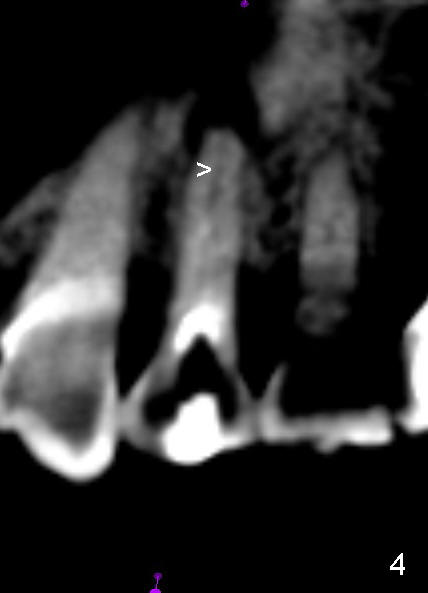

A 72-year-old lady has a deep cervical defect of the tooth #12 (Fig.1 ^) associated with buccal apical fistula (*) and periapical radiolucency (Fig.2 *). To prevent bleach leakage during root canal therapy (RCT), composite is used to repair the defect (Fig.3 (CT coronal section) C) prior to access. The buccal canal is not located probably due its own or iatrogenic (due to composite) obliteration. After thorough debridement of the lingual canal, Calcium Hydroxide paste is placed (*).

A month later, the fistula disappears (Fig.5). Effort is exerted without success to find the obliterated canal, including increasing access and removing the portion of composite which may block the opening of the canal. RCT is finished. Two months postop, the patient returns for prophy. She remains asymptomatic. There is no recurrent infection. Seven months post RCT, periapical radiolucency seems to have disappeared (Fig.6), whereas the fistula does not recur (Fig.7).